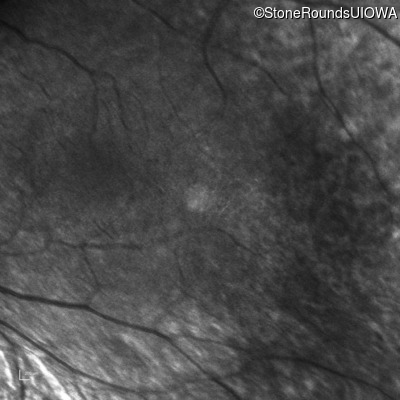

Infrared Fundus Photograph - Right -

No Light Perception

Exemplar

Expanded OCT Stack

×